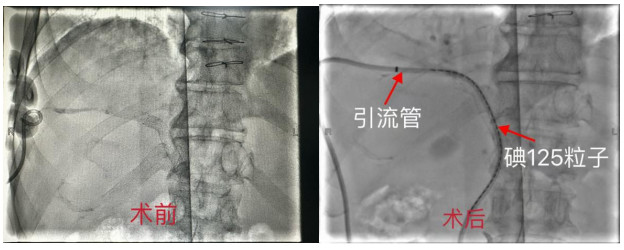

核医学科团队为史先生制定了周密的手术方案,采用“经皮穿肝刺胆管术(PTCD)+胆道放射性粒子植入术”。手术中,医生通过微创手术,成功引流了胆汁,并将30枚放射性碘125粒子精准植入肿瘤部位,对肿瘤进行“精准打击”。术后,史先生的恢复情况良好,肝功能指标基本恢复正常,生活质量得到了显著提升。

核医学科团队经过研究,决定采用新型一体化可携带碘125粒子的胆道内外引流管技术,为史先生进行治疗。这根看似普通的引流管,实则暗藏“玄机”:它不仅能快速排出淤积的胆汁,还能精准释放放射性粒子,持续杀灭肿瘤细胞,从根源上降低胆道再梗阻风险,实现了“胆汁引流+肿瘤放疗”的同步治疗。